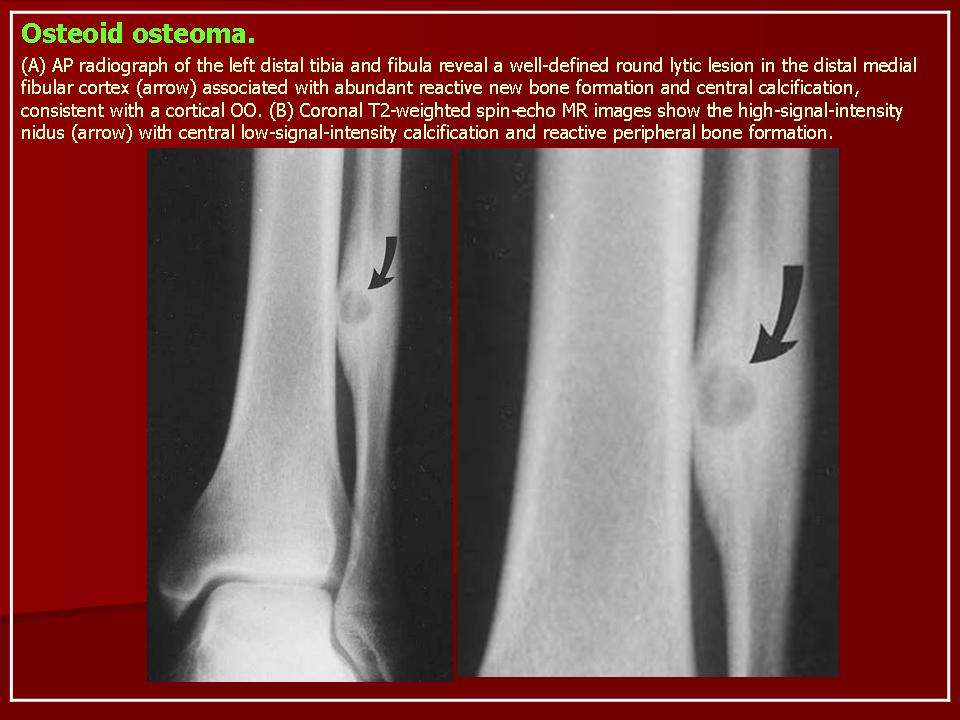

Рентгенологическая картина остеоид-остеомы весьма характерна. Рентгенологические симптомы возникают значительно позже клинических проявлений опухоли, и первым на рентгенограмме обнаруживают склероз кости. На участке поражения формируется одностороннее или муфтообразное утолщение кости в виде гиперостоза. Позднее в толще гиперостоза формируется основной отличительный признак остеоид-остеомы - ее «гнездо» в виде очага разрежения диаметром до 1 см, внутри которого могут отмечаться мелкие костные включения. Сквозь слой склерозированной ткани «гнездо» опухоли на обычных рентгенограммах не всегда дифференцируется и для ее выявления применяют лучи повышенной жесткости и томографию. Обнаружение «гнезда» необходимо для подтверждения диагноза и проведения направленного оперативного вмешательства.